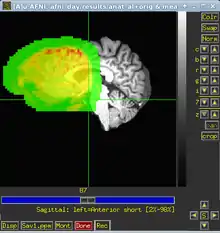

AFNI is a command line based tool, i.e. all the processing steps are defined in a script, using commands and methods built-in to afni, which is then run on the data. You can but don't have to put up your scripts from scratch, afni_proc.py and uber-subject.py (see below) are helpful tools to help you putting together your processing script. Afni does have a graphical viewer for images and graphs. Once you have installed AFNI (check tutorial below or [1]) and entered AFNI environment by typing AFNI, you can call this GUI by typing

to you terminal. It will try to find and open Afni or Nifti format datasets in your current folder and otherwise open on a default anatomical image. The tutorial mentioned below gives a good introduction to how you can use the viewer to inspect you data before, during and after processing.

Otherwise, probably due to different mosaic centers, your coregistration may end up looking something like this: